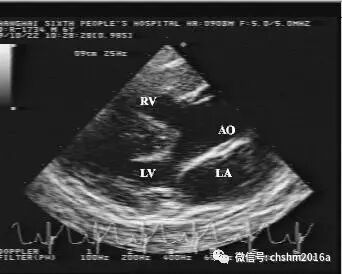

1.二维和M型超声心动图

左室长轴切面见主动脉增宽前移,其前壁与室间隔连续性中断,右室前壁及室间隔增厚,大动脉短轴切面可显示狭窄的漏斗部、肺动脉瓣及左右肺动脉。

彩超伪像是什么先天性心脏病超声诊断(超声梦影像医生集团 CCM)_https://www.jmylbn.com_新闻资讯_第13张

图2.3.11   显示室间隔缺损和骑跨的主动脉

LV:左室  LA:左房  AO:主动脉  RV:右室